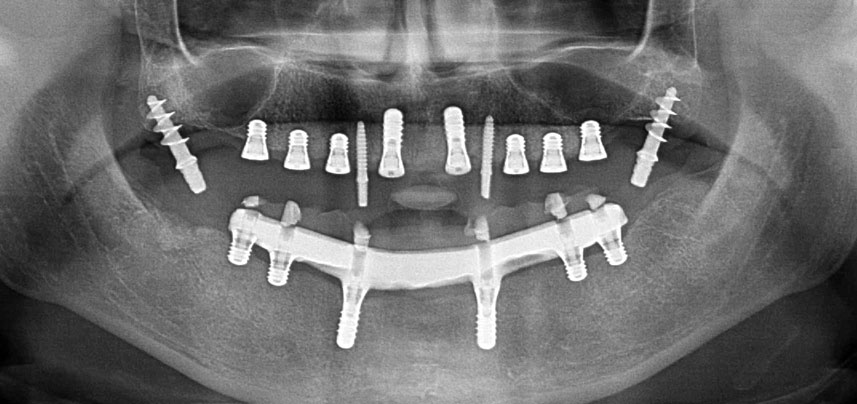

Три години по-късно е дошло времето за максиларна протеза от същия тип. Въз основа на планирането със CBCT, аугментацията на синусите е избегната с помощта на къси импланти и използването на хирургичен шаблон, за да се прехвърлят планираните позиции в алвеоларния гребен. (Фиг. 1 и 2).

Постоперативна панорамна ренгенография

Фиг. 10 Постоперативна панорамна ренгенография показва всички импланти в подходящи позиции, включително временните птеригоидни импланти.